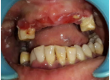

Systemic lupus erythematosus (SLE) presents as a chronic inflammatory autoimmune disease that can often demonstrate multisystem involvement. Since, immune-suppressive drugs are used in the treatment of this disease, it can possess an elevated risk of infection and delay healing. Moreover, damage to the salivary glands in this disease leads to reduced salivation. Together, these complications can be a primary concern in dental treatment procedures owing to inability to maintain oral hygiene and risk of implant failure. This is the first case report in literature to our knowledge and it represents a treatment option and procedure for immediate full mouth rehabilitation after extraction without raising flaps using basal cortical screw implant in a patient who was on corticosteroid for over 20 years as she was diagnosed with Systemic Lupus Erythematosus. Since there are very few cases of SLE reported in literature with the use of oral implants, treating these patients can often pose a challenge.